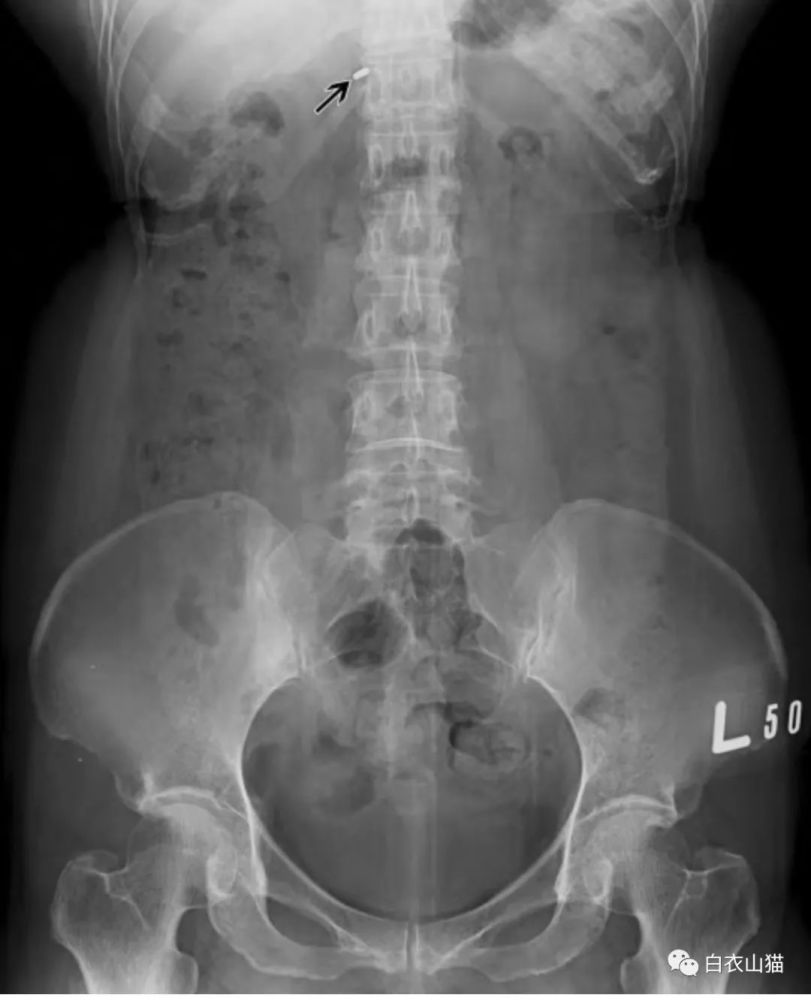

结肠癌钡灌肠后,肠穿孔,手术结果已公布.2012.12.19

证实腹腔有积液存在,急诊探查显示腹水为血性腹水1000ml,无穿孔征象

肠穿孔的x线表现图片

肠穿孔腹部平片图片